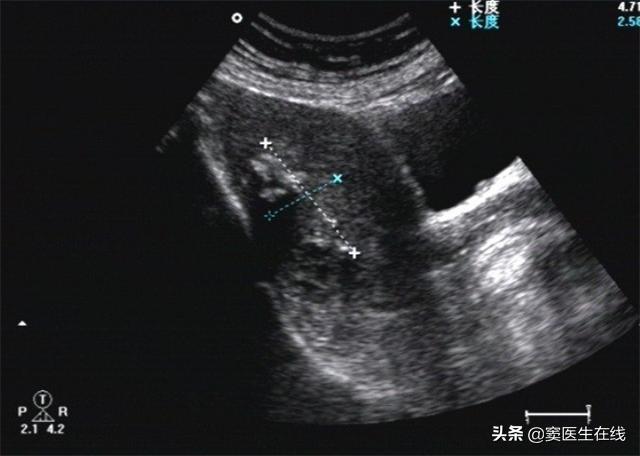

患者体温36.8℃、血压132/89、身高159cm、体重72kg。B超提示子宫内膜双层厚3.8mm,回声欠均匀。宫腔镜检查:子宫内膜厚,子宫内膜多个息肉样增生,宫颈外口可见一直径3cm息肉样物脱出,表面不平整,质地脆。MRI检查提示符合子宫内膜癌并腹水表现,左侧卵巢体积增大。子宫内膜组织病理学检查提示为子宫内膜癌早期。